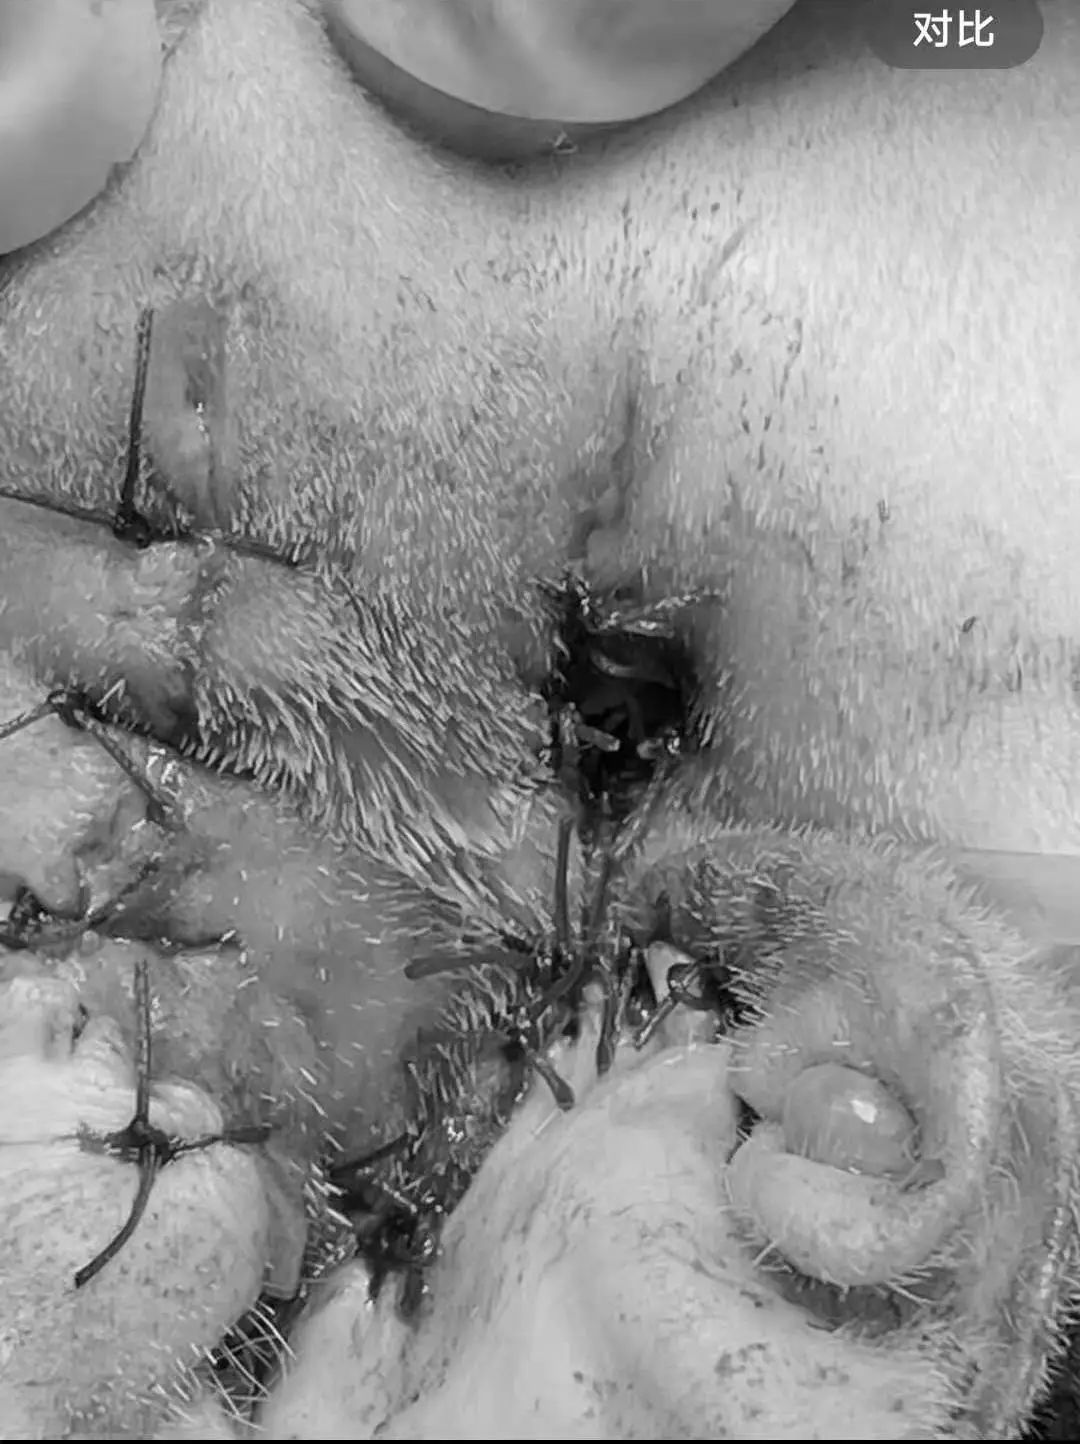

术后缝合伤口

手术取出组织送检病理排除肿瘤风险。

对样本进行细菌培养,药敏试验,菌种鉴定,结果显示感染菌未大肠埃希菌,后续根据药敏针对性输液抗感染治疗。